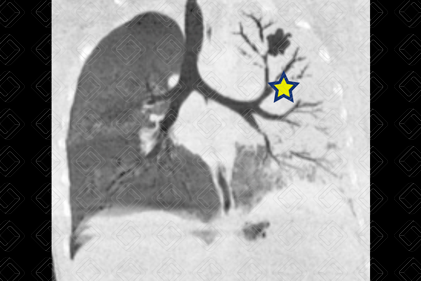

Texto alternativo para a imagem Figura 2. Créditos: Dra. Elazir Mota - Rio de Janeiro/RJ

Descrição da figura 2: Caso 1: Tomografia computadorizada do tórax foi realizada para melhor avaliação, evidenciando a presença de extensa consolidação esquerda que justifica o hemitórax opaco de volume mantido deste lado (asterisco).